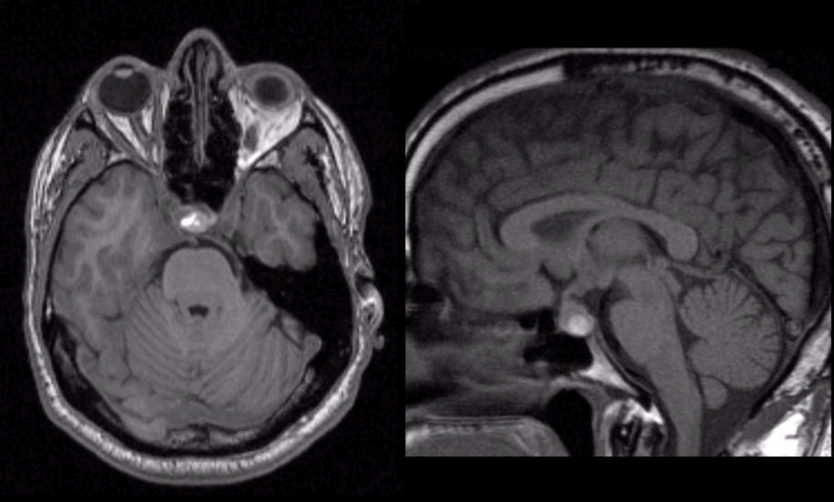

colloid cyst

benign but can cause acute hydrocephalus